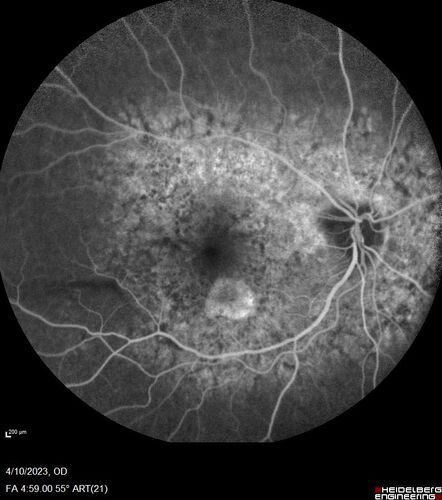

Bietti's Crystalline Dystrophy - CYP4V2 homozygous

58-year-old-female (from Thailand)

Patient had evaluation for LASIK and there was concern that the BCVA was not normal.

PMHx Benign, Meds: none

VA 20/25 OU